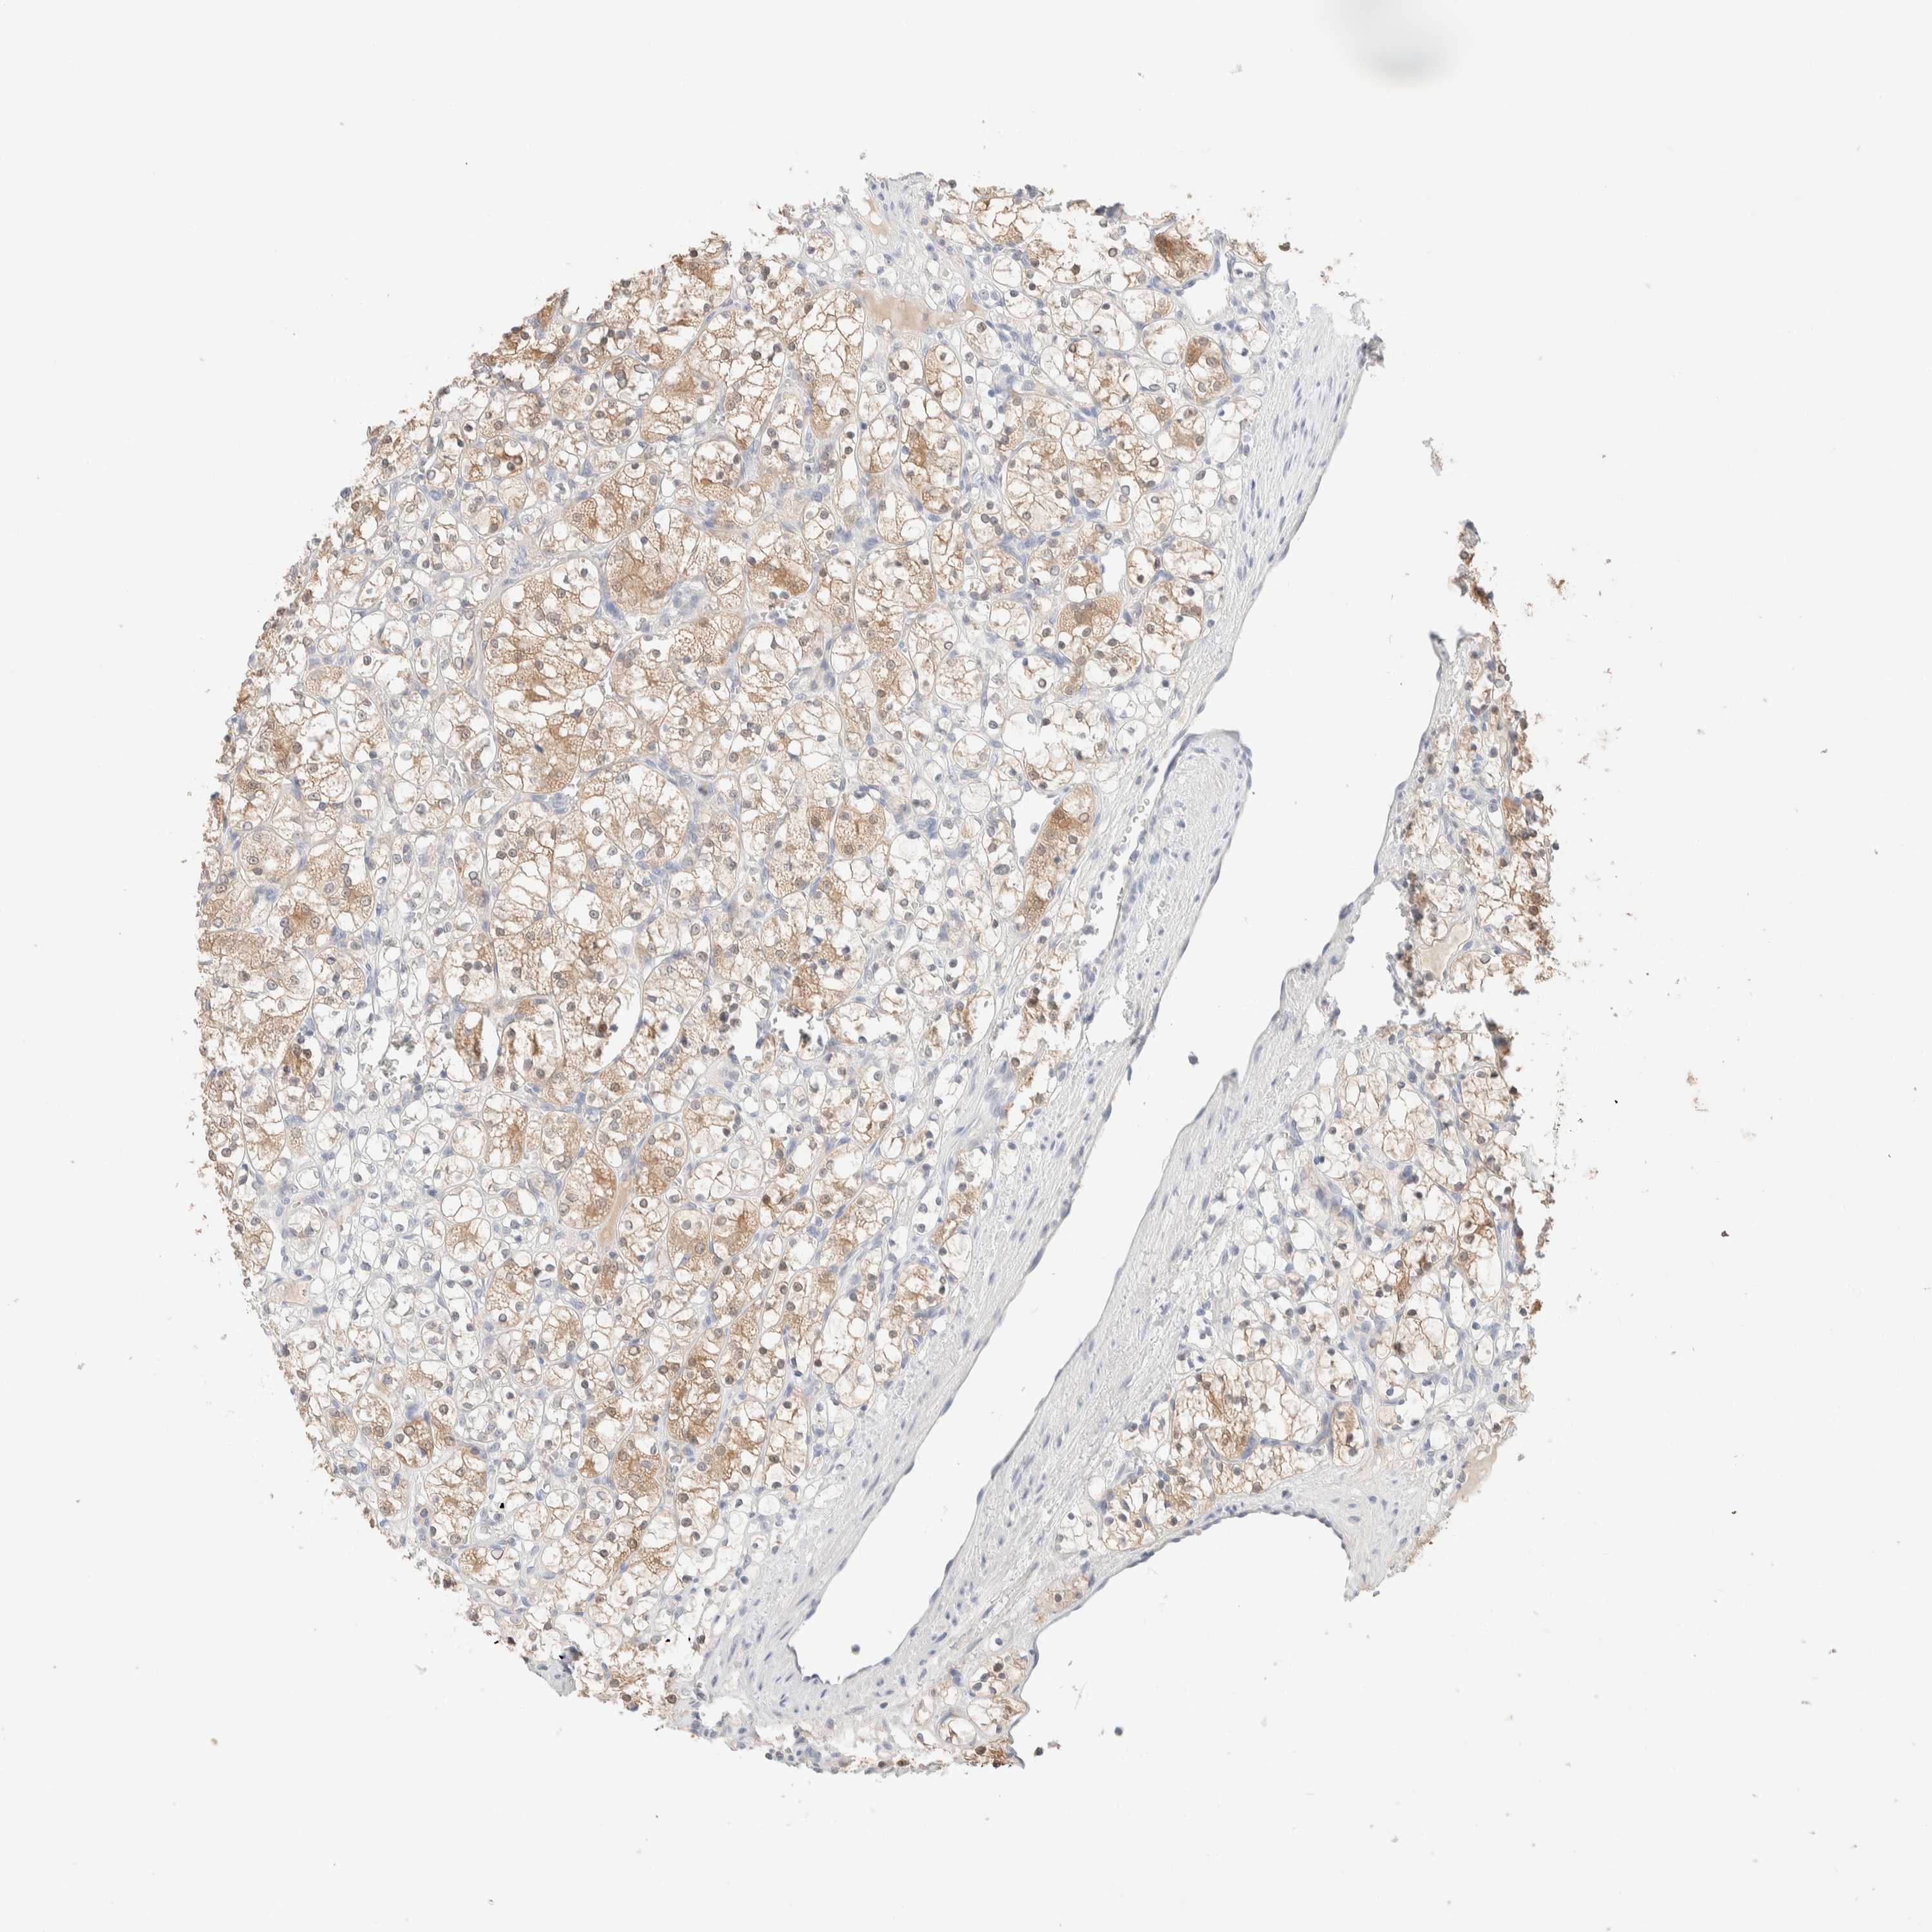

KIDNEY CHROMOPHOBE (TCGA) - Interactive survival scatter ploti

The Survival Scatter plot shows the clinical status (i.e. dead or alive) for all individuals in the patient cohort, based on the same data that underlies the corresponding Kaplan-Meier plots. Patients that are alive at last time for follow-up are shown in blue and patients who have died during the study are shown in red.

The x-axis shows the expression levels (FPKM) of the investigated gene in the tumor tissue at the time of diagnosis. The y-axis shows the follow-up time after diagnosis (years). Both axes are complimented with kernel density curves demonstrating the data density over the axes. The top density plot shows the expression levels (FPKM) distribution among dead (red) and alive patients (blue). The right density plot shows the data density of the survived years of dead patients with high and low expression levels respectively, stratified using the cutoff indicated by the vertical dashed line through the Survival Scatter plot. This cutoff is automatically defined based on the FPKM cutoff that minimizes the p-score. The cutoff can be changed by dragging the vertical line or by entering a cutoff value in the square labeled "Current cut-off".

Under the Survival Scatter plot the p-score landscape (black curve; left axis) is shown together with dead median separation (red curve; right axis). Dead median separation is the difference in median mRNA expression between patients who have died with high and low expression, respectively. It is calculated as follows: median FPKM expression of dead patients with high expression - median FPKM expression of dead patients with low expression. This is intended to aid the user in visually exploring custom cutoffs and the associated p-scores and dead median separation.

Individual patient data is displayed and can be filtered by clicking on one or more of the category buttons on the top of the page. Categories describing expression level and patient information include: high, low, alive, dead, female, male and tumor stages. The scale of the x-axis can be toggled between linear and log-scale by clicking on the "x log" button. Mouse-over function shows TCGA ID, patient information and mRNA expression (FPKM) for each patient.

& Survival analysisi

Kaplan-Meier plots summarize results from analysis of correlation between mRNA expression level and patient survival. Patients were divided based on level of expression into one of the two groups "low" (under cut off) or "high" (over cut off). X-axis shows time for survival (years) and y-axis shows the probability of survival, where 1.0 corresponds to 100 percent.

RIDA is not prognostic in Kidney Chromophobe (TCGA)

: 27.63

Average pTPM 25.7

Number of samples 64